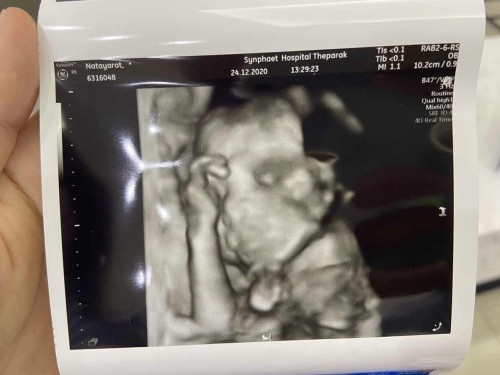

ทีมเมษาค่า ซาวด์ตอน21 weeks ตอนนี้ 24weeks แล้วค่า น้องผู้ชาย โตตามเกณฑ์ แข็งแรงดีค้าบ

กำหนด22เมษาค่ะ หมอบอกน้ำหนักน้องตามเกณฑ์ น้องเปนผู้ชายค่ะ👶

464กรัมค่า กำหนดคลอด25เมษา หรืออาจจะก่อนค่ะ